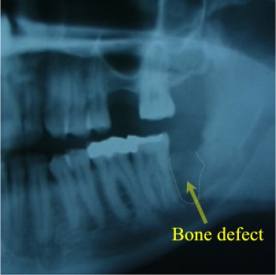

Alternatively, the other question you should ask yourself is ‘What are the risks of not doing surgery and leaving the wisdom teeth behind? When the wisdom teeth erupt through the gums completely, and are able to reach the proper, healthy position in the jawbone, there is little risk in keeping them or ‘not doing surgery’. These properly positioned wisdom teeth are only slightly more likely to develop cavities or gum disease as compared to the other back-teeth in your mouth. However, when a wisdom tooth is impacted or malpositioned, the tooth and associated gum can be very susceptible to bacterial infection, localized gum disease, and gum abscesses. These problems sometimes occur with very little associated pain or discomfort. In such cases, the gum disease and/or infection will progress ‘silently’ until the tooth in front of the wisdom tooth, along with its supporting gum and bone tissue, is damaged. (see figures 2 and 3)

X-ray Picture of Figure2

Alternativley, impacted or malpositioned wisdom teeth can cause a painful jaw infection with facial swelling, jaw stiffness and pus drainage. Waiting until pain or infection occurs, can result in irreversible damage to adjacent teeth, gum, and the tooth-supporting bone of the jaw. This is why it is often suggested to have wisdom teeth removed early before these events occur. As well, early removal in younger patients can result in more complete healing of any damaged tissues afterwards as compared to removal when patients are older.

Bony Defect Left After Wisdom Tooth Extraction in Older Patient